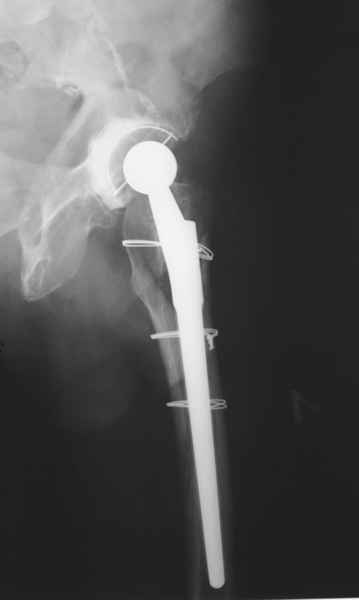

Произведено закрытое удлинение ножки эндопротеза с помощью ретроградного интрамедуллярного стержня. Продолжительность операции 3 часа. Два из них закрытое восстановление длины бедра диистрактором

таз-бедро.

А нельзя ли увидеть и профиль бедра на всем протяжении, т.е. и весь протез, и весь стержень? И фас бы с коленом.

новые снимки

Пациента удалось осмотреть недавно. Достигнутый результат сохраняется. Перелом бедра сросся. Конечность опорная и безболезненная, ходит без трости. Ножка, похоже, реинтегрировалась, как и надеялись. Снимки и фото в приложении. Комментарии приветствуются.

Надо ли что-то делать дальше, как полагаете? Убрать винты? Убрать "удлинитель ножки"? Или оставить все, как есть? Спасибо заранее.